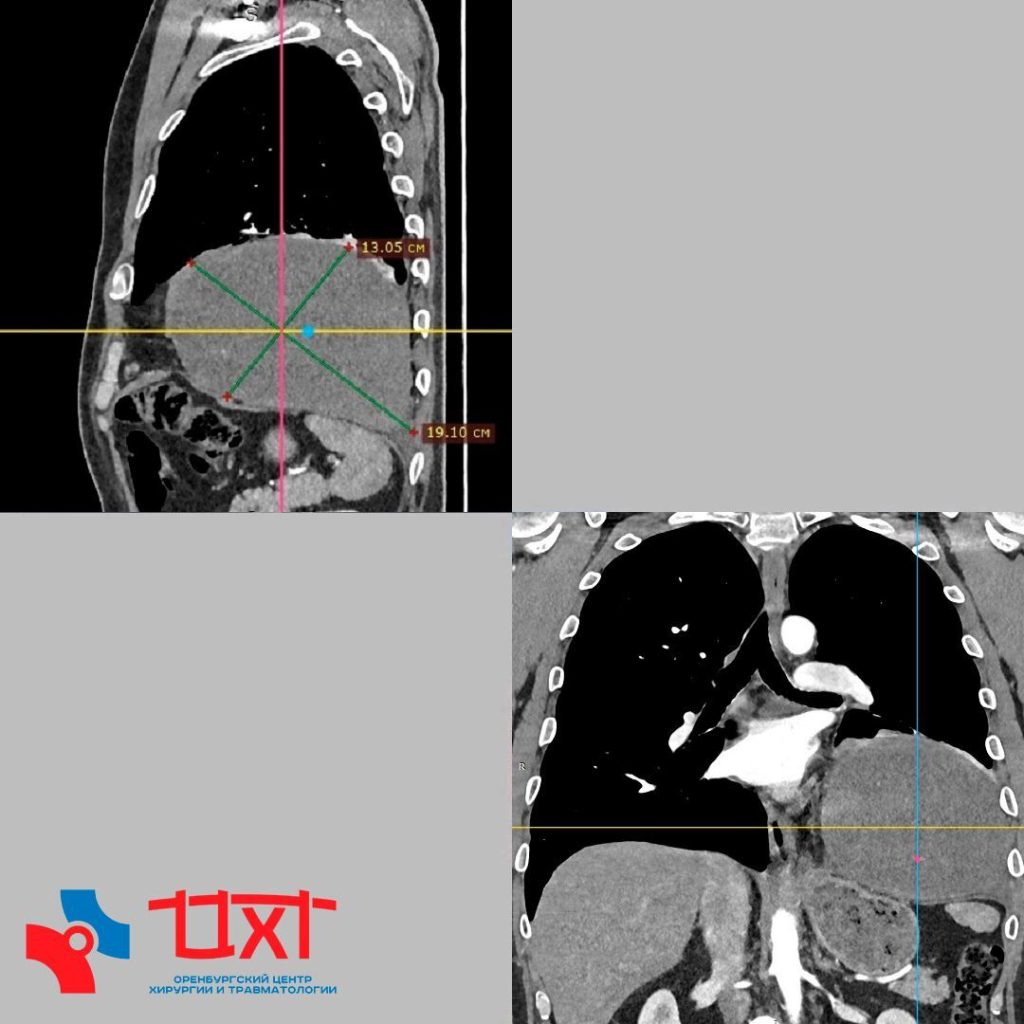

По данным КТ с контрастированием, опухоль размером 13×19×12 см плотно прилегала к перикарду, диафрагме и нижней доле левого легкого, вызвав его ателектаз. Несмотря на внушительные размеры новообразования, внутригрудные лимфоузлы не были поражены.